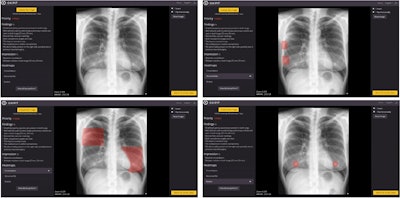

Image of patient (upper-left) in which, according to the radiologist's report, there is only consolidation, but the algorithm detects an abnormal rib (upper-right), consolidation (lower-left), and two nodules (lower-right). It is worth noting the confusion of a consolidation with mammary tissue and of two nodules with the two mammary areolae. Image courtesy of Scientific Reports.

ChestEye uses a computer-aided diagnosis (CAD) algorithm that analyzes x-rays for 75 different findings and localizes the features on images as heatmaps. It can also generate preliminary text reports that incorporate relevant findings in chest x-ray images.